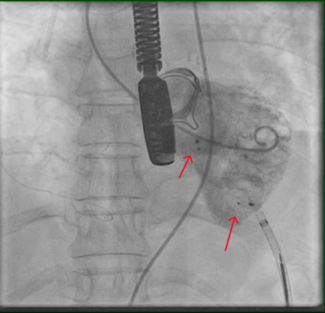

A 59-year-old man was referred to our institution for potential MitraClip (Abbott Vascular) therapy after he was found to have severe mitral regurgitation (MR) seen on transthoracic echocardiography. He had a history of coronary artery disease and functional MR, and underwent coronary artery bypass grafting and mitral annuloplasty (28 mm CG Future; Medtronic Inc.) 4 years prior at an outside institution. A permanent pacemaker was also implanted for advanced atrioventricular block. The procedure was complicated by a methicillin-resistant  staph aureus sternal wound infection requiring multiple debridements and wound vacuum drainage for 1 year. There was no documented bacteremia at that time. Three years later, he had several admissions for decompensated heart failure, volume overload, and pulmonary edema without angina pectoris. Transthoracic echocardiogram revealed left ventricular (LV) ejection fraction of 55%, severe MR with 2 distinct regurgitant jets, and an estimated right ventricular pulmonary systolic pressure of 60 mm Hg. Subsequent transesophageal echocardiography (TEE) demonstrated a dilated mitral annulus with the septal-lateral dimension measuring 36 mm. There was significant dehiscence of the annuloplasty ring from the posterior annulus and focal dehiscence at the right fibrous trigone, with a resultant 6 x 8 mm perforation at the base of the anterior mitral leaflet (Figure 1). There was 4+ MR through the mitral leaflet perforation and 1+ central MR. There was trivial regurgitation through the posterior dehiscence (Figure 2). After referral to our center, 3.5 years after the original operation, several blood cultures drawn on different days were negative and an erythrocyte sedimentation rate was normal. Angiography demonstrated occluded vein grafts to the left circumflex and right coronary arteries with severe native diffuse disease not amenable to percutaneous or surgical revascularization. The left internal mammary artery graft to left anterior descending artery was patent. In view of his related comorbidities and prior sternal wound infection, percutaneous repair of the anterior mitral leaflet perforation was performed.

staph aureus sternal wound infection requiring multiple debridements and wound vacuum drainage for 1 year. There was no documented bacteremia at that time. Three years later, he had several admissions for decompensated heart failure, volume overload, and pulmonary edema without angina pectoris. Transthoracic echocardiogram revealed left ventricular (LV) ejection fraction of 55%, severe MR with 2 distinct regurgitant jets, and an estimated right ventricular pulmonary systolic pressure of 60 mm Hg. Subsequent transesophageal echocardiography (TEE) demonstrated a dilated mitral annulus with the septal-lateral dimension measuring 36 mm. There was significant dehiscence of the annuloplasty ring from the posterior annulus and focal dehiscence at the right fibrous trigone, with a resultant 6 x 8 mm perforation at the base of the anterior mitral leaflet (Figure 1). There was 4+ MR through the mitral leaflet perforation and 1+ central MR. There was trivial regurgitation through the posterior dehiscence (Figure 2). After referral to our center, 3.5 years after the original operation, several blood cultures drawn on different days were negative and an erythrocyte sedimentation rate was normal. Angiography demonstrated occluded vein grafts to the left circumflex and right coronary arteries with severe native diffuse disease not amenable to percutaneous or surgical revascularization. The left internal mammary artery graft to left anterior descending artery was patent. In view of his related comorbidities and prior sternal wound infection, percutaneous repair of the anterior mitral leaflet perforation was performed.

Initially, right heart catheterization was performed that demonstrated pulmonary arterial pressure of 40/20 with mean pulmonary capillary wedge pressure of 18 mm Hg and V waves up to 22 mm Hg. Simultaneously, left heart catheterization revealed LV end diastolic pressure of 17 mm Hg, ruling out mitral stenosis. A BRK needle (St. Jude Medical) was used to perform transseptal puncture under echocardiographic guidance and a Mullins transseptal sheath (Medtronic Inc.) was advanced through the interatrial septum in a superior location within the fossa ovalis. Intravenous heparin was given at this point. Mean left atrial pressure was recorded at 18 mm Hg with prominent V waves up to 40 mm Hg. The Mullins sheath was then removed and a medium curl Agilis NxT catheter (11.5 Fr outer diameter, 8.5 Fr inner diameter, St. Jude Medical) was advanced into the left atrium and directed toward the base of the anterior mitral leaflet. Through the Agilis catheter, an 8 Fr EBU 3.75 guiding catheter (Medtronic Inc.) was then advanced to its tip. Another multipurpose catheter was then nested through the guiding catheter using a triple telescoping “mother and child” approach. An exchange-length 0.035˝ angled Glidewire (Terumo Medical Corporation) was then advanced through the leaflet perforation using three-dimensional TEE guidance in an antegrade fashion. Over the Glidewire, the multipurpose catheter was passed through the defect into the LV apex. The Glidewire was then exchanged for an Amplatz Superstiff wire (Boston Scientific), over which the EBU guiding catheter was advanced in the LV cavity (Figure 2). Once the guiding catheter was appropriately positioned in the LV midcavity, the multipurpose catheter as well as the stiff wire were removed. Then, a 5 mm Amplatzer atrial septal occluder was loaded into the guiding catheter and deployed successfully to the anterior mitral leaflet perforation under TEE guidance (Figure 3). On color Doppler, there was no residual MR through the leaflet perforation and only 1+ functional (central) MR with excellent device stability (Figures 1 and 4). The anterior mitral leaflet had preserved mobility and there was no obstruction of the LVOT (Figure 4). Mean left atrial pressure after the repair was 15 mm Hg with diminished V waves. Final transmitral gradient was 4 mm Hg with mitral valve area of 2.5 cm2. Procedural fluoroscopy time was 27 minutes. The postprocedure course was uneventful and the patient was discharged on aspirin and clopidogrel on postprocedure day 1. At 1-month follow-up, he was in New York Heart Association functional class I. He developed transient mild hemolytic anemia, which did not require transfusion. On follow-up echocardiogram, there was no residual MR through the defect and only 1+ central MR.

Initially, right heart catheterization was performed that demonstrated pulmonary arterial pressure of 40/20 with mean pulmonary capillary wedge pressure of 18 mm Hg and V waves up to 22 mm Hg. Simultaneously, left heart catheterization revealed LV end diastolic pressure of 17 mm Hg, ruling out mitral stenosis. A BRK needle (St. Jude Medical) was used to perform transseptal puncture under echocardiographic guidance and a Mullins transseptal sheath (Medtronic Inc.) was advanced through the interatrial septum in a superior location within the fossa ovalis. Intravenous heparin was given at this point. Mean left atrial pressure was recorded at 18 mm Hg with prominent V waves up to 40 mm Hg. The Mullins sheath was then removed and a medium curl Agilis NxT catheter (11.5 Fr outer diameter, 8.5 Fr inner diameter, St. Jude Medical) was advanced into the left atrium and directed toward the base of the anterior mitral leaflet. Through the Agilis catheter, an 8 Fr EBU 3.75 guiding catheter (Medtronic Inc.) was then advanced to its tip. Another multipurpose catheter was then nested through the guiding catheter using a triple telescoping “mother and child” approach. An exchange-length 0.035˝ angled Glidewire (Terumo Medical Corporation) was then advanced through the leaflet perforation using three-dimensional TEE guidance in an antegrade fashion. Over the Glidewire, the multipurpose catheter was passed through the defect into the LV apex. The Glidewire was then exchanged for an Amplatz Superstiff wire (Boston Scientific), over which the EBU guiding catheter was advanced in the LV cavity (Figure 2). Once the guiding catheter was appropriately positioned in the LV midcavity, the multipurpose catheter as well as the stiff wire were removed. Then, a 5 mm Amplatzer atrial septal occluder was loaded into the guiding catheter and deployed successfully to the anterior mitral leaflet perforation under TEE guidance (Figure 3). On color Doppler, there was no residual MR through the leaflet perforation and only 1+ functional (central) MR with excellent device stability (Figures 1 and 4). The anterior mitral leaflet had preserved mobility and there was no obstruction of the LVOT (Figure 4). Mean left atrial pressure after the repair was 15 mm Hg with diminished V waves. Final transmitral gradient was 4 mm Hg with mitral valve area of 2.5 cm2. Procedural fluoroscopy time was 27 minutes. The postprocedure course was uneventful and the patient was discharged on aspirin and clopidogrel on postprocedure day 1. At 1-month follow-up, he was in New York Heart Association functional class I. He developed transient mild hemolytic anemia, which did not require transfusion. On follow-up echocardiogram, there was no residual MR through the defect and only 1+ central MR.